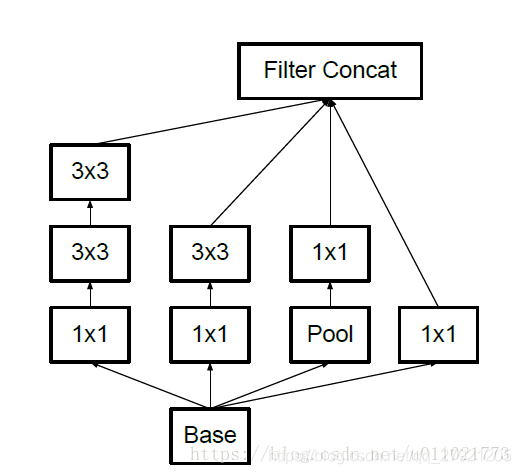

提出了新的模块Ice module: